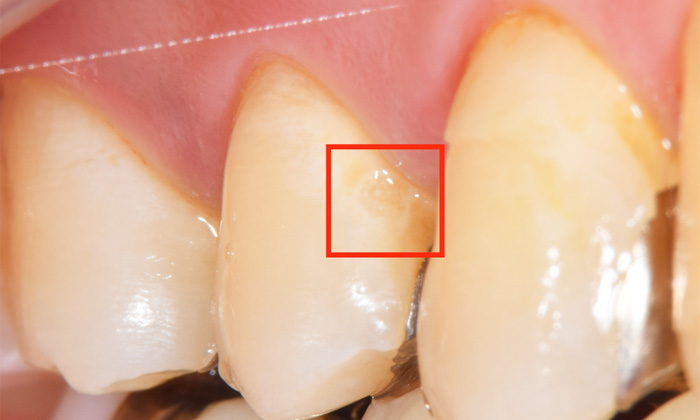

こちらの写真ですが、赤枠部分がC1です。歯のエナメル質が溶けて、歯がかけ始めている状態です。

なかなか見ただけでは判断が難しく、ただの着色と思えるかもしれませんが、実際に触ってみると、ざらざらしており、明らかに歯が溶けてしまっているとわかります。

麻布十番歯科で虫歯部位を赤枠で囲った症例写真